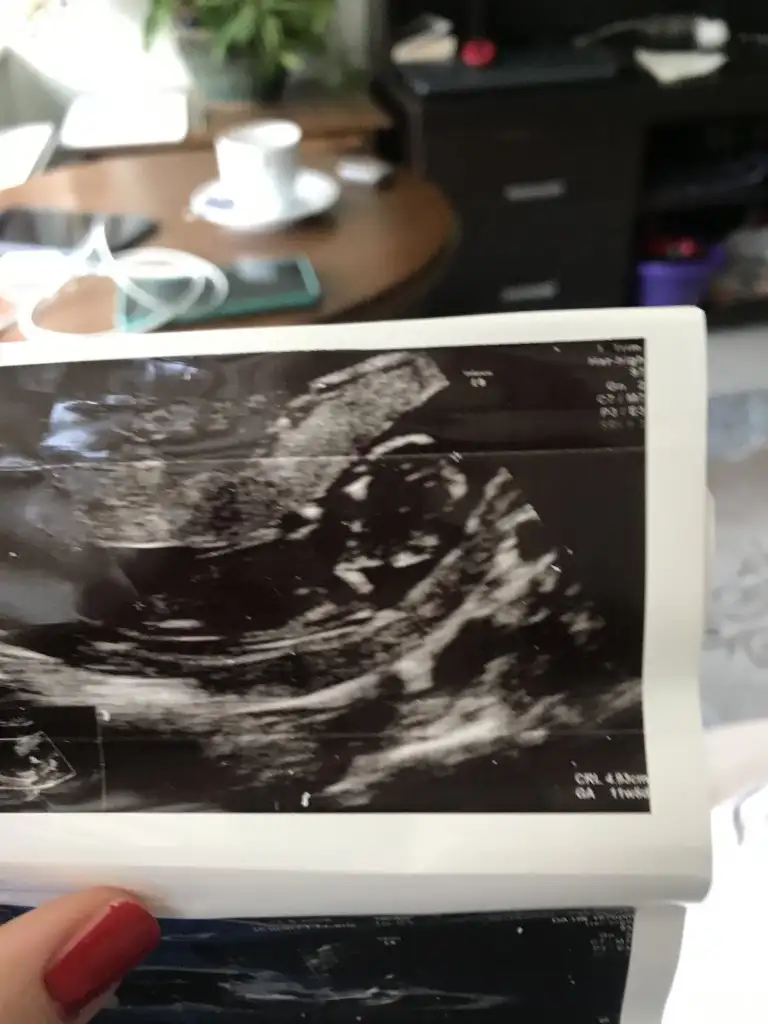

12+2 bana da yorum yaparmısınız, doğru gönderebildim mi bilemiyorumDr + tam nuba denk getirmiş başka usg varmı![]()

12+2 günlük, bana da yorum yapabilir misiniz

Kız gibi